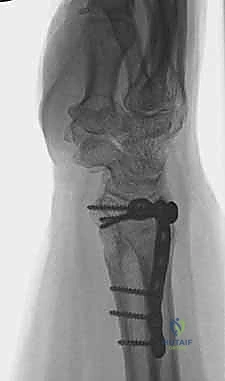

1. الأشعة السينية (X-rays): بوضعيات متعددة (أمامية خلفية، وجانبية دقيقة). الوضعية الجانبية الحقيقية (True Lateral) حاسمة لاكتشاف أي خلع جزئي في المفصل (DRUJ).

2. الأشعة المقطعية ثلاثية الأبعاد (3D CT Scan): تُستخدم في الكسور المفتتة أو كسور رأس الزند المفصلية المعقدة، حيث تعطي خريطة دقيقة للجراح قبل الدخول لغرفة العمليات.

ثانياً: العلاج الجراحي (Surgical Intervention)

خطوات التدخل الجراحي الدقيق مع الأستاذ الدكتور محمد هطيف

تُعد جراحات المعصم والزند من الجراحات الدقيقة التي تتطلب مهارة عالية، وهو المجال الذي يتفوق فيه الأستاذ الدكتور محمد هطيف بفضل استخدامه لتقنيات الجراحة المجهرية (Microsurgery) والأدوات الجراحية ذات التقنية العالية.

يقوم الدكتور هطيف بدراسة الأشعة المقطعية ثلاثية الأبعاد بدقة، ويختار نوع وحجم الصفائح المعدنية (Plates) والمسامير (Screws) المناسبة لكل مريض بناءً على حجم العظم ونوع الكسر.